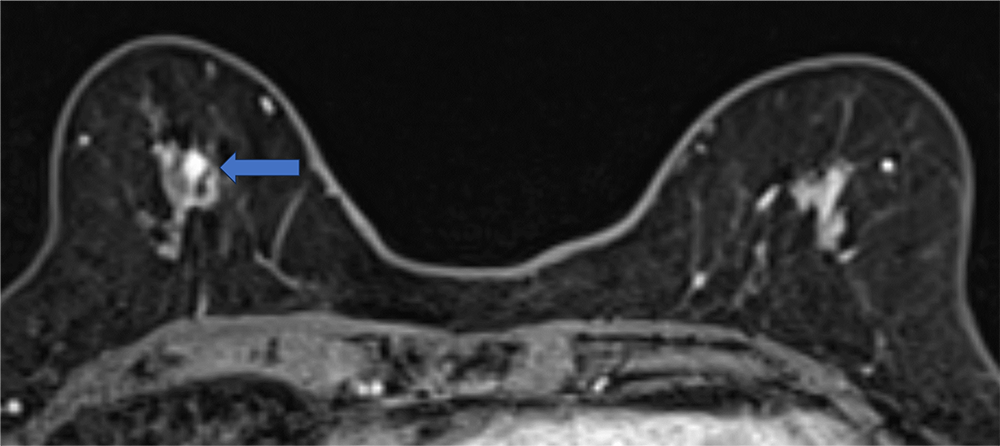

4. ダイナミックMRI 造影前 早期相 遅延相

病変は扁平な形状で均一に増強される。ダイナミックMRIの増強パターンはfast and plateauであった。

ダイナミックMRI 早期相

ダイナミックMRI 遅延相